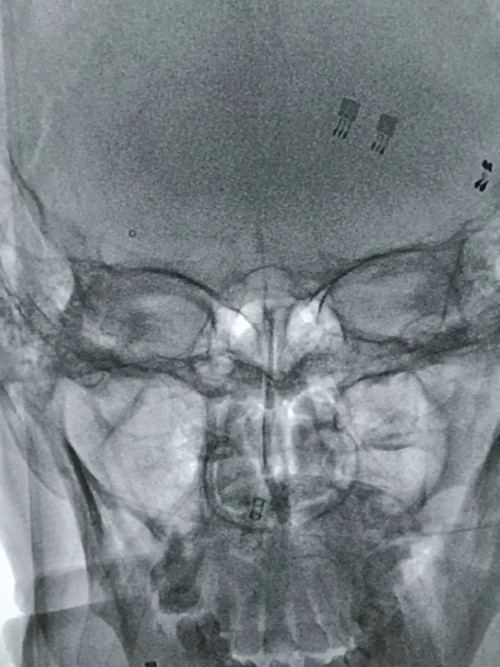

静脉溶栓治疗效果不明显,医生紧急启动介入治疗,为抢救患者生命争分夺秒。介入中心主任李光雷及副主任王振兴为患者急诊行血管造影检查,结果显示右颈内动脉起始段严重钙化斑块并闭塞。

右颈内动脉起始段严重钙化斑块并闭塞